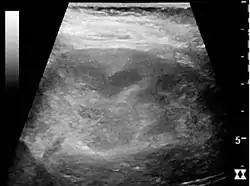

Complex cysts can have membranes dividing the fluid-filled center with internal echoes, calcifications or irregular thickened walls. The complex cyst can be further evaluated with Doppler US, and for Bosniak classification and follow-up of complex cysts, either contrast-enhanced ultrasound (CEUS) or contrast CT is used (Figure 6). The Bosniak classification is divided into four groups going from I, corresponding to a simple cyst, to IV, corresponding to a cyst with solid parts and an 85–100% risk of malignancy.[1] In polycystic kidney disease, multiple cysts of varying size in close contact with each other are seen filling virtually the entire renal region. In advanced stages of this disease, the kidneys are enlarged with a lack of corticomedullary differentiation (Figure 7).[1]

Figure 6. Complex cyst with thickened walls and membranes in the lower pole of an adult kidney. Measurements of kidney length and the complex cyst on the US image are illustrated by '+' and dashed lines.[1]